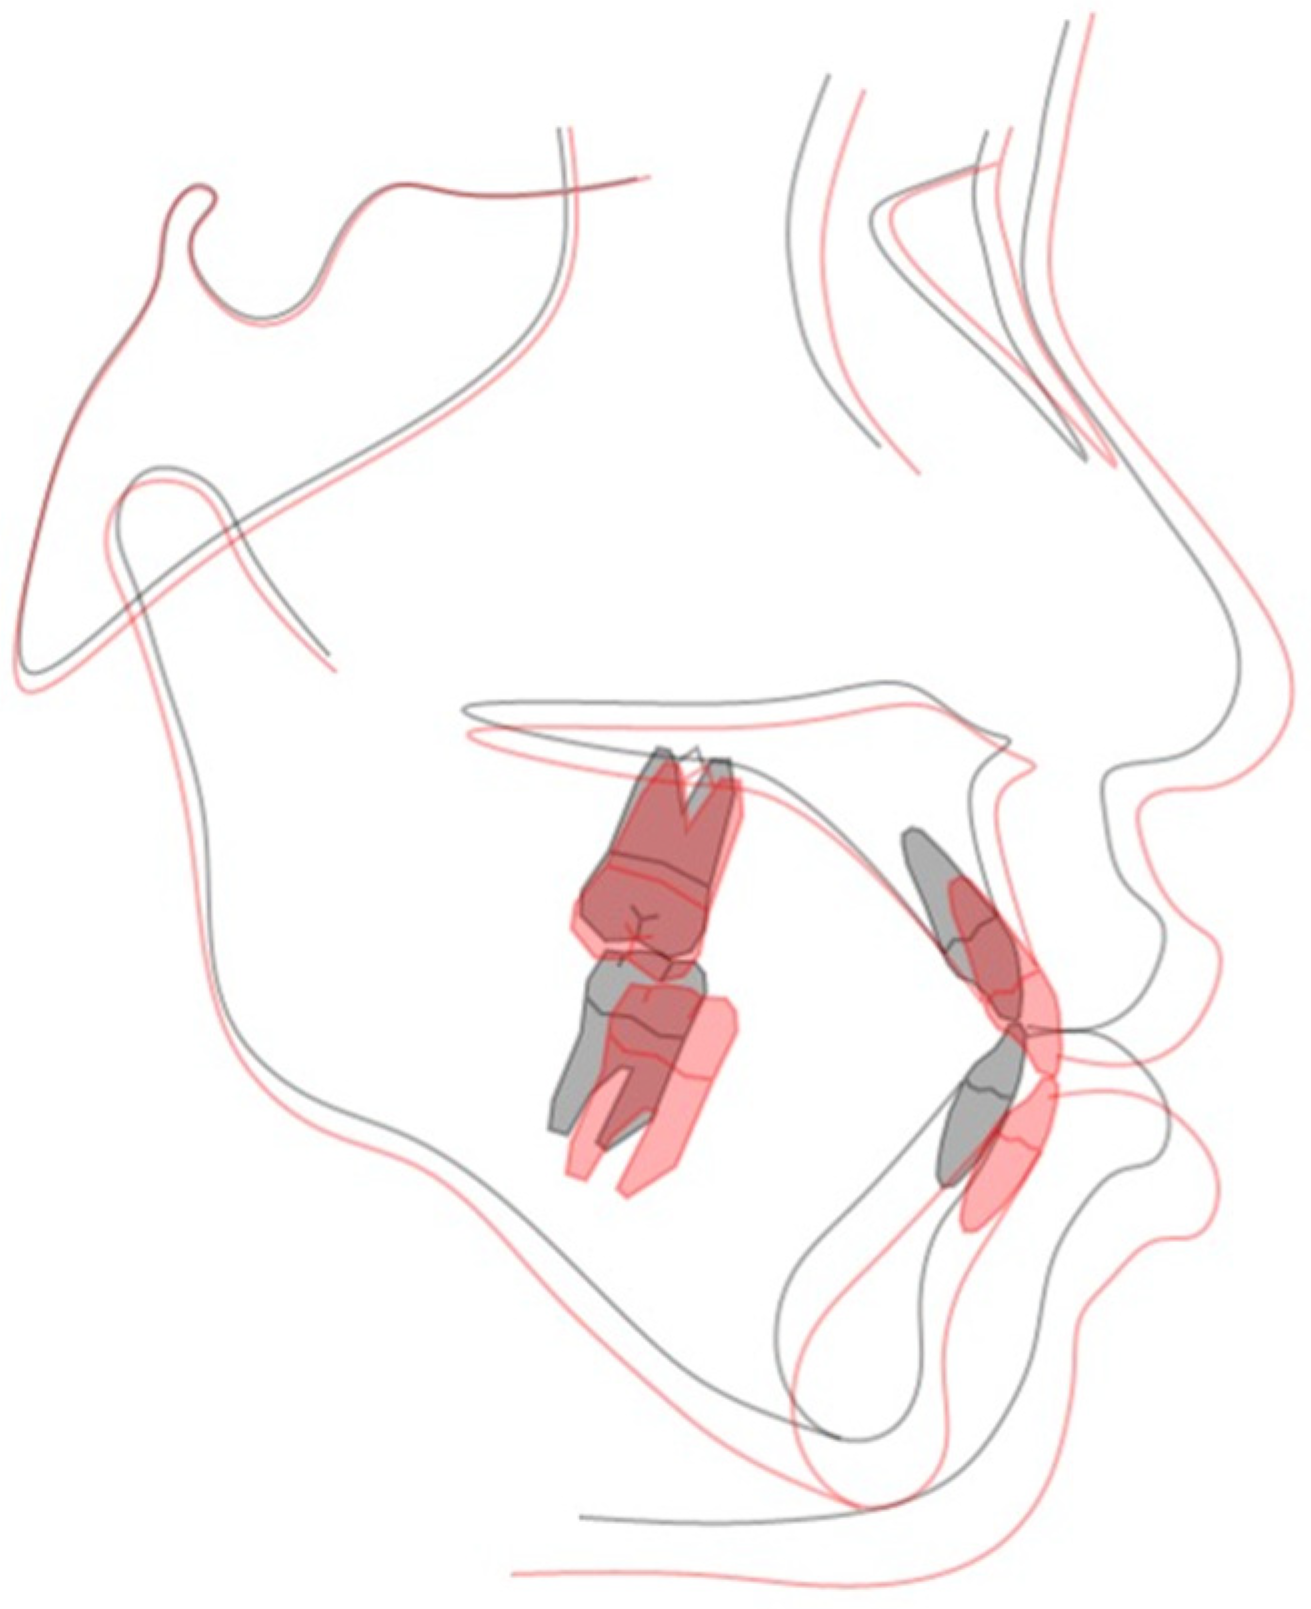

2.4. Treatment Progress